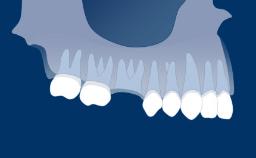

Os pacientes desejam dentes com boa saúde, função, estética e fonética. Quando indicado para dentes ausentes, os implantes dentários são um meio para atender a esses requisitos. Este Módulo de Aprendizagem delineará as geometrias dos implantes e suas características que visam facilitar a integração com os tecidos duros e moles, permitindo que eles sirvam como elementos de ancoragem para reconstruções protéticas enquanto também resistem às forças de carga oclusal.

A geometria do corpo dos implantes geralmente pode ser dividida em três partes: a parte endóssea, que se encontra dentro do osso, a seção transmucosa, que fica nos tecidos moles entre o osso e a cavidade oral, e a interface com os componentes protéticos. Em cada uma dessas três partes, existem outras características da geometria e variações na sua forma, atributos e dimensões. Existem também variações no material do corpo do implante e no tratamento de superfície. Essas variações serão descritas e discutidas nos seguintes Objetivos de Aprendizagem.